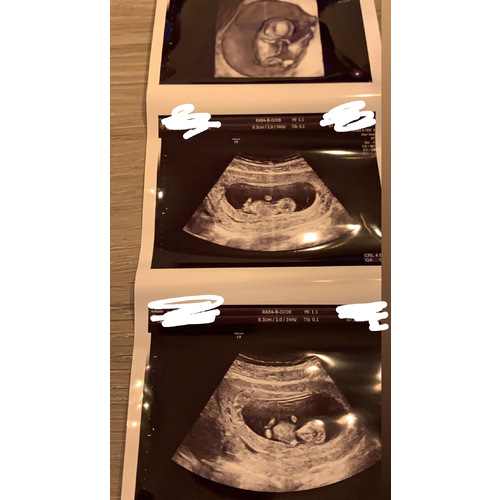

Wat een mooie echo's! Ik zou me er geen zorgen over maken hoor er is altijd vanalles te zien vooral bij een 3d/4d echo. Zolang de verloskundige niets heeft gezegt zou ze niets geks hebben gezien.

De Nub is het geslachts knobbeltje dit wordt een vagina of penis, even heel simpel uitgelegd 🥰

Dat je schommelt qua dagen klopt een mm ernaast meten en het scheelt weer iets met de dagen🤪👍🏻

Rond de 12 weken doen ze vaak de definitieve meting en deze blijven ze dan als richtlijn aanhouden ☺️ dan is de kleine wat groter en kunnen ze beter meten.